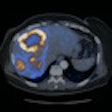

DOPA-PET/CT can alter therapy for neuroendocrine tumors

January 14, 2010